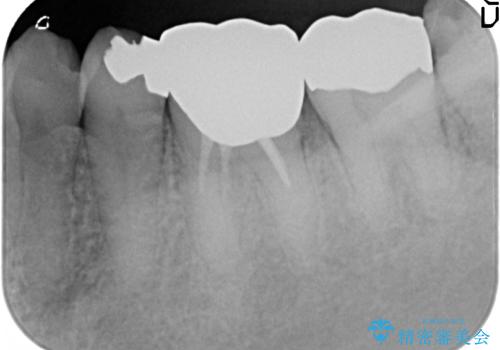

- 左下の奥歯が激しく痛むので診て欲しいといらっしゃった方の症例です。

他院で相談したところ抜歯を提案されたが、歯を抜かずに済む方法はないかと当院にいらっしゃいました。

検査の結果左下6に根尖病変を認めたため、再根管治療を行いました。

その後症状の消失を確認し、オールセラミッククラウンによる補綴を行いました。